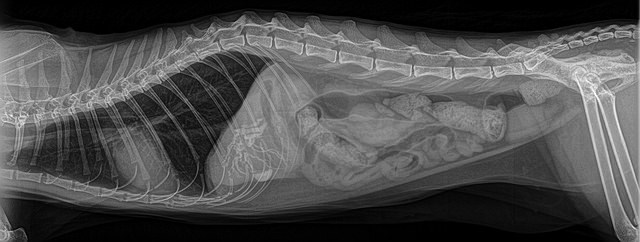

Проводится осмотр Вашего питомца на предмет дискомфорта в животе, с обязательным прослушиванием сердцебиения. Делается рентген брюшной полости и малого таза для определения наличия посторонних предметов, и, если предмет обнаруживают, определяют его размеры.

- рентгенологическое исследование.